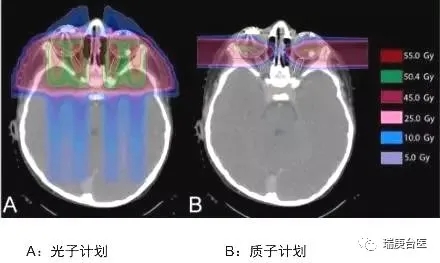

这是头颈部肿瘤剂量分布图比较,我们明显能看到两者的差异,常规放疗蓝色区域很大,说明射线对病灶周边的正常组织有不可避免的损害,质子放疗可以减少咽喉和口腔部位的放疗损伤,降低发生口角炎、口腔炎、吞咽困难、口干的发生率。